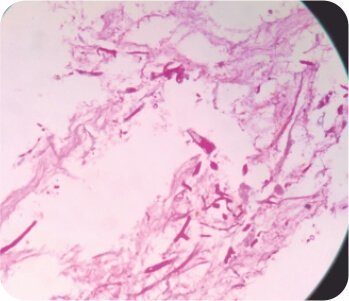

Cryobiopsy of the protruding mass suggestive of invasive mucor mycosis (Broad aseptate hyphae)